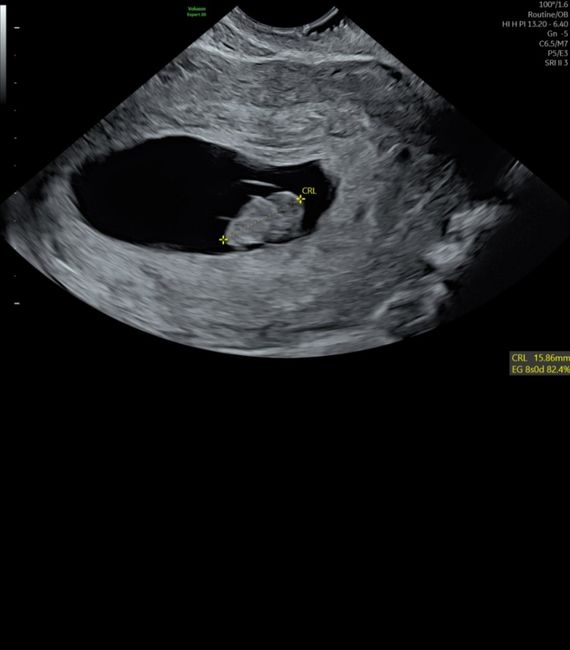

Hola! Quería preguntaros si entendéis el método Ramzi si sabéis que puede ser. Os lo agradecería muchísimo. Es una ecografía de 7 semanas

Hola, es una eco transvaginal de 7+3, según el método que sería?

Graciaass!!!Método Ramzi 7